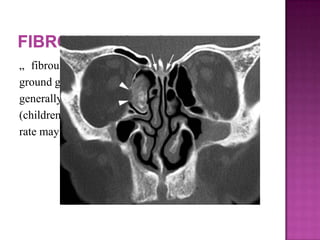

„ fibrous dysplasia characteristically has a

ground glass appearance on CT images. . It

generally presents in younger patients

(children and adolescents), and its growth

rate may decrease or stop after puberty